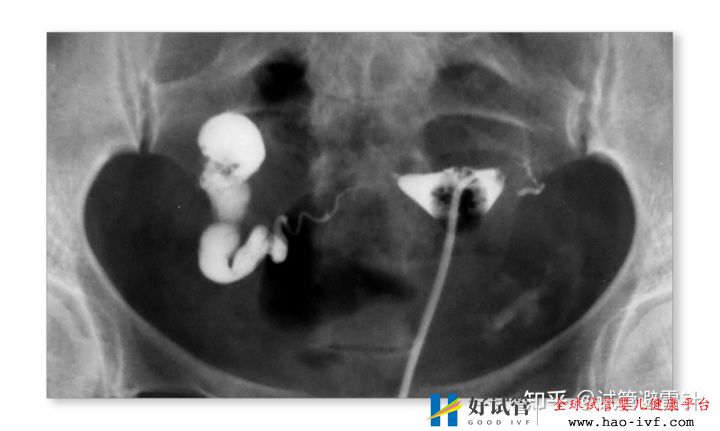

2.严重的输卵管疾病,如盆腔炎引起的输卵管堵塞和积水;或输卵管结核,子宫内膜却正常的患者;或异位妊娠手术后的输卵管堵塞。

1.女性各种因素造成的配子运输障碍

如输卵管缺如、双侧输卵管阻塞、严重盆腔粘连或输卵管手术史等输卵管功能丧失;单侧输卵管通畅,如复发性出现对侧卵巢排卵、卵巢储备功能下降者等,应适度放宽“试管婴儿指征”。